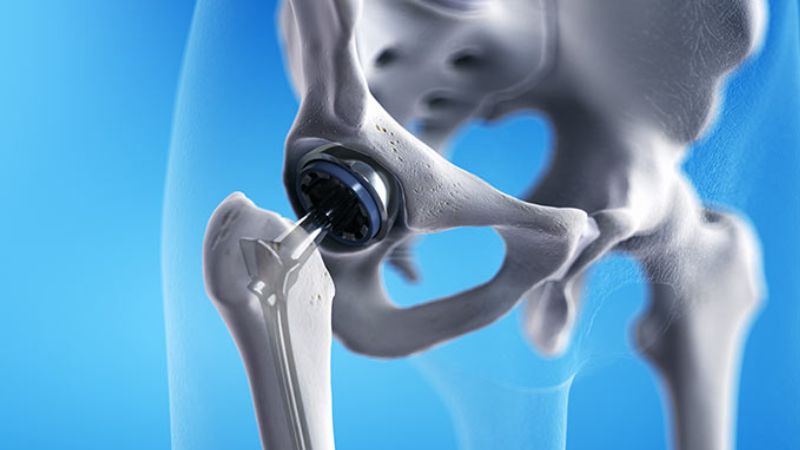

- Thay khớp nhân tạo: Khi tổn thương xương quá nghiêm trọng và không thể phục hồi, bác sĩ sẽ tiến hành thay thế hoàn toàn khớp bị hư hỏng bằng một khớp nhân tạo để phục hồi chức năng vận động.

Thay khớp nhân tạo có thể được chỉ định nếu xương bị tổn thương nghiêm trọng